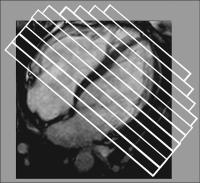

Abbildung 1: Planung der Kurzachsenschnitte: Lage der Schnitte zur Erstellung der Kurzachsen - Cineloops perpendikular zur horizontalen Achse (HLA). Abstand der Schichten: 10 mm